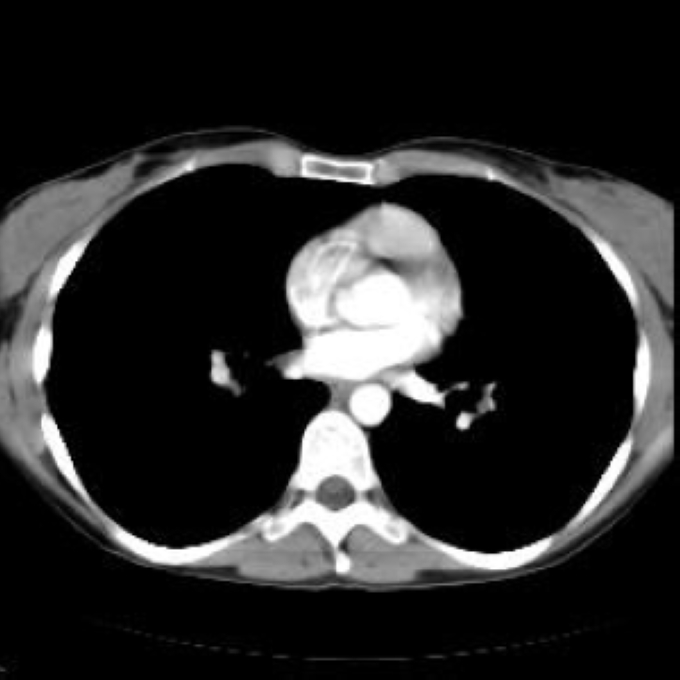

56 jaehrige Patientin mit Schluckbeschwerden.

Im konventionellen Roentgen-Thorax auffaellige Weichteilformation

im oberen Mediastinum beschrieben.

Was ist diese Raumforderung im oberen Mediastinum?